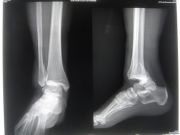

Malleolus fracture

Malleolus fracture is one of the most common fracture in the human body.

For this fracture we use several classifications like: Lauge-Hansen, Weber, AO. Malleolus fracture could be stable or not. The treatment of stable fracture, that can not be displaced under the influence of normal forces, could be conservative (cast, black walker boot).

About unstable fracture surgical management is the only option (O.R.I.F- Open Reduction Internal Fixation). In the surgical field a variety of implants could be used like plates, screws, K-w and cerclage wire.